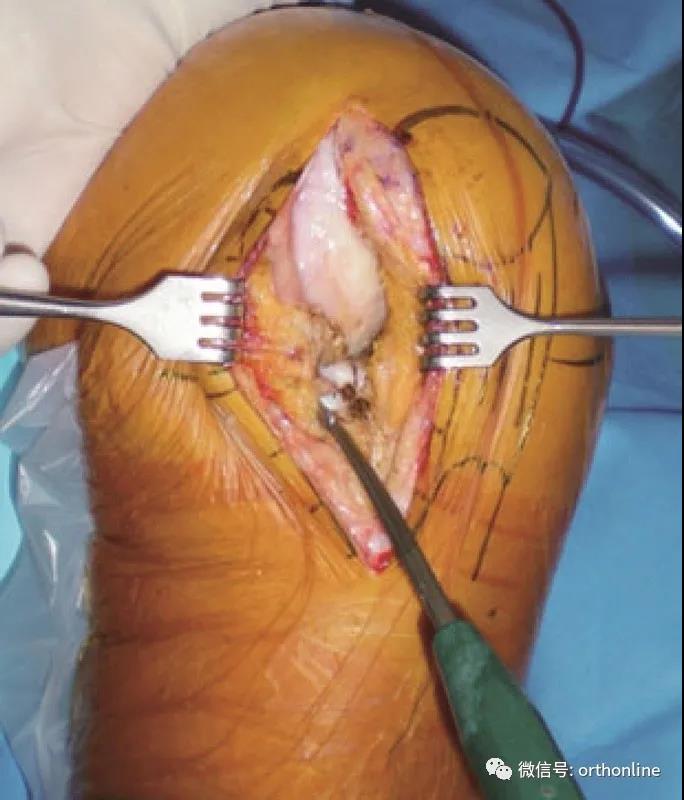

截骨后放入试模,测试轨迹